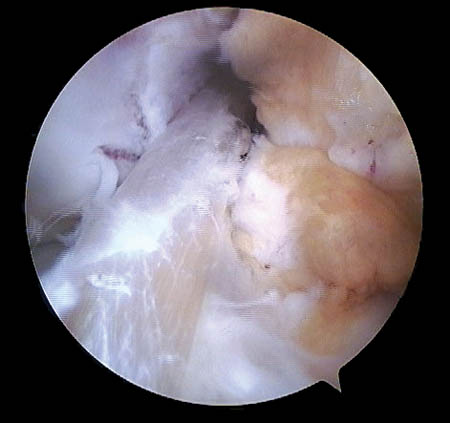

Respecto a su morfología usamos la clasificación de Lage et al.28 (Figs. 9, 10 y 11) que se distribuyeron de la siguiente manera:

-

58.6% Colgajo radial.

26.1% Fibrilada.

14.2% Longitudinal periférica.

1.1% Inestables.

Figura 10: Lesión labral por mecanismo Pincer.